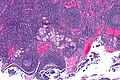

Xanthogranulomatous lymphadenitis

Xanthogranulomatous lymphadenitis is an uncommon pathology of the lymph node.

Microscopic

Features: